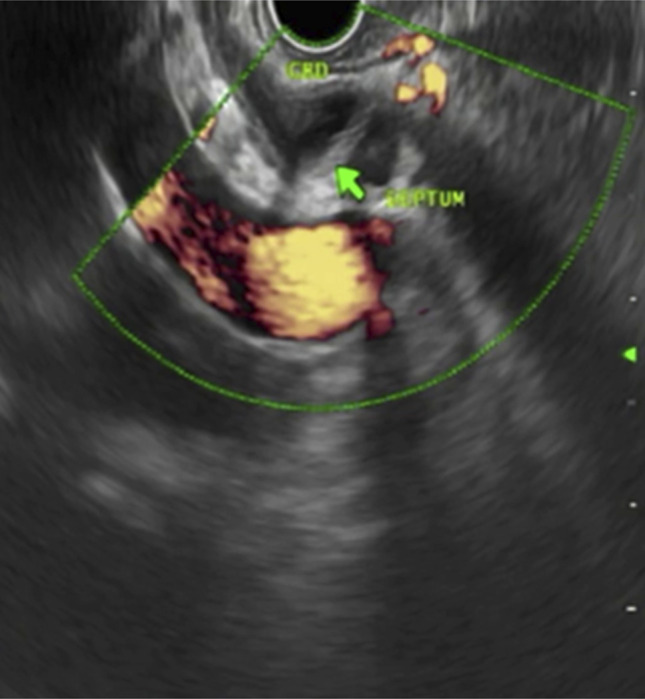

This is the first reported case demonstrating endoscopic ultrasound (EUS) findings in type Va duplication. The malformation of the congenital extrahepatic bile duct is classified as type Va and is rarely observed. To date, not more than 30 cases have been reported in Western literature. For the medical literature, a 50-year-old man with a type Va extrahepatic bile duct obstruction is examined. He presented with abdominal pain and jaundice, and imaging showed biliary dilatation and cholelithiasis. During the EUS procedure, an endoscopic examination revealed the presence of a duplicated common bile duct with a septum. Endoscopic retrograde cholangiopancreatography of the biliary tract also showed the same anomaly, with the presence of obstructive biliary sludge. The case highlights the need to consider EUS as a potent alternative diagnostic method. It is important to detect these anomalies immediately to reduce the chances of endoscopic/surgical complications.

Abstract Image